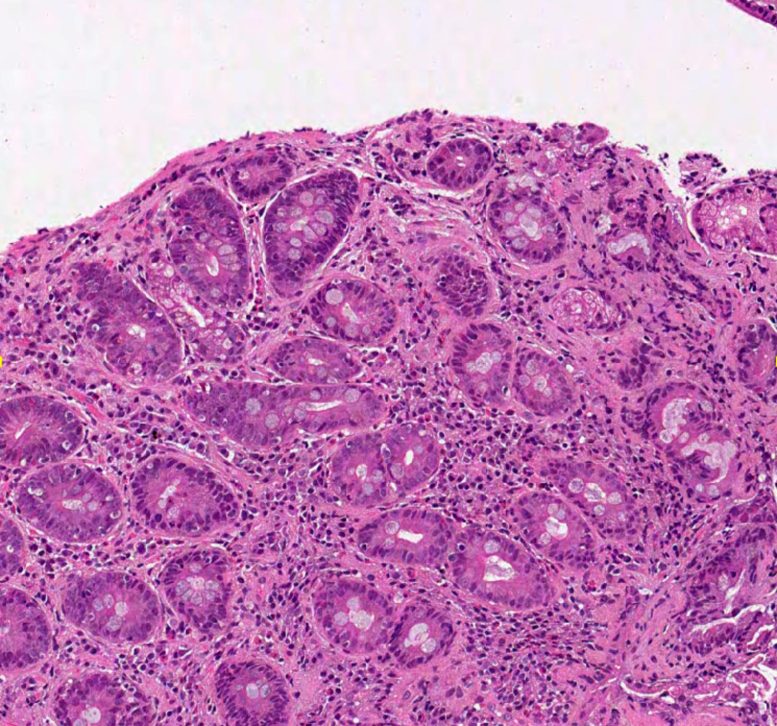

The gold standard for diagnosing celiac disease is via a biopsy of the duodenum (part of the small intestine). Pathologists will then analyze the sample under a microscope or on a computer to look for damage to the villi, tiny hair-like projections that line the inside of the small intestine.

Interpreting biopsies, which often have subtle changes, can be subjective. Pathologists use a classification system known as the Marsh-Oberhuber scale to judge the severity of a case, ranging from zero (the villi are normal and the patient is unlikely to have the disease) to four (the villi are completely flattened).

“Elizabeth came to our meeting to talk about her research. It was quite fun because she showed us pictures of biopsies and said could we guess which were celiac and which weren’t? It wasn’t easy.”